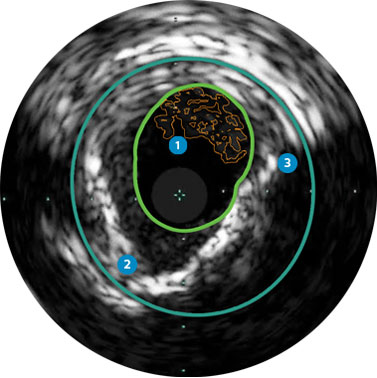

Behandlungsplan Beispiel 2

Lumen mit frischem Thrombus

Mikrokalzifizierung

Kalzifizierte Plaque mit Schallschatten

Gefässgrösse: 6 mm Durchmesser Plaquemorphologie: gemischte, thrombotische Plaque mit mittlerem Calcium Plaquegeometrie: exzentrische Läsion Position des Führungsdrahtes: wahres Lumen

Quick-Cross-Katheter: souverän komplexe Morphologien durchqueren Turbo-Power-Laser-Atherektomie: vorwärts gerichtetes, direktionales Abtragen zur Beseitigung von Thromben; Rotation für verbessertes Abtragen in kalzifizierten Läsionen AngioSculpt Scoring-Ballonkatheter: sicheres Aufweiten von Reststenosen4 Stellarex DCB: entwickelt für hohe Leistungsfähigkeit bei Kalfizifierungen